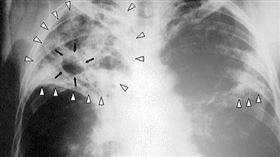

吃飯唱KTV都恐染結核病!潛伏期高達50年

結核病(TB)在台灣歷史上曾造成衝擊,可透過空氣與飛...